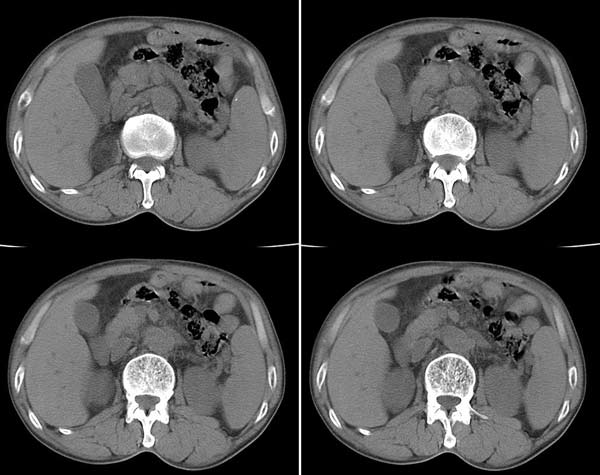

病人手下肢水肿,血压正常,无其他异常表现.

b超发现右肾上腺区占位,ct平扫见由肾上腺低密度占位性病变,病灶边界清楚,密度不均,ct值-20--60hu.

不做增强很难诊断。平扫看右肾上腺内支低密度占位与肾上级分不清,病变大体呈椭圆形,内有囊性部分,也有实性部分。考虑为嗜络细胞瘤

从值上看,考虑肾上腺骨髓脂肪瘤.不除外肾上极错构瘤.扫描层面好象不连续并且扫描厚.

右肾上腺低密度结节,无明显脂肪成分,临床无高血压,可除外肾上腺骨髓脂肪瘤及嗜络细胞瘤,考虑肾上腺腺瘤

右肾上腺低密度结节,ct -20----60hu .临床无高血压,可除外嗜络细胞瘤,考虑肾上腺髓样脂肪瘤或无功能性腺瘤[水肿提示病变引起肾上腺功能低下]

有明显的脂肪成分,考虑骨髓脂肪瘤。

右肾上腺低密度结节影,显然密度较低和脂肪差不多未见高密度分隔考虑肾上腺原醛腺瘤,建议临床检查相关的生化指标。脾大,并见高密度钙化点。

肾上腺内含有脂肪成份,可以定性为骨髓脂肪瘤。

肾上腺肿瘤可以肯定,没有强化,很难定性,但从平扫特点多考虑无功能性肾上腺腺瘤.